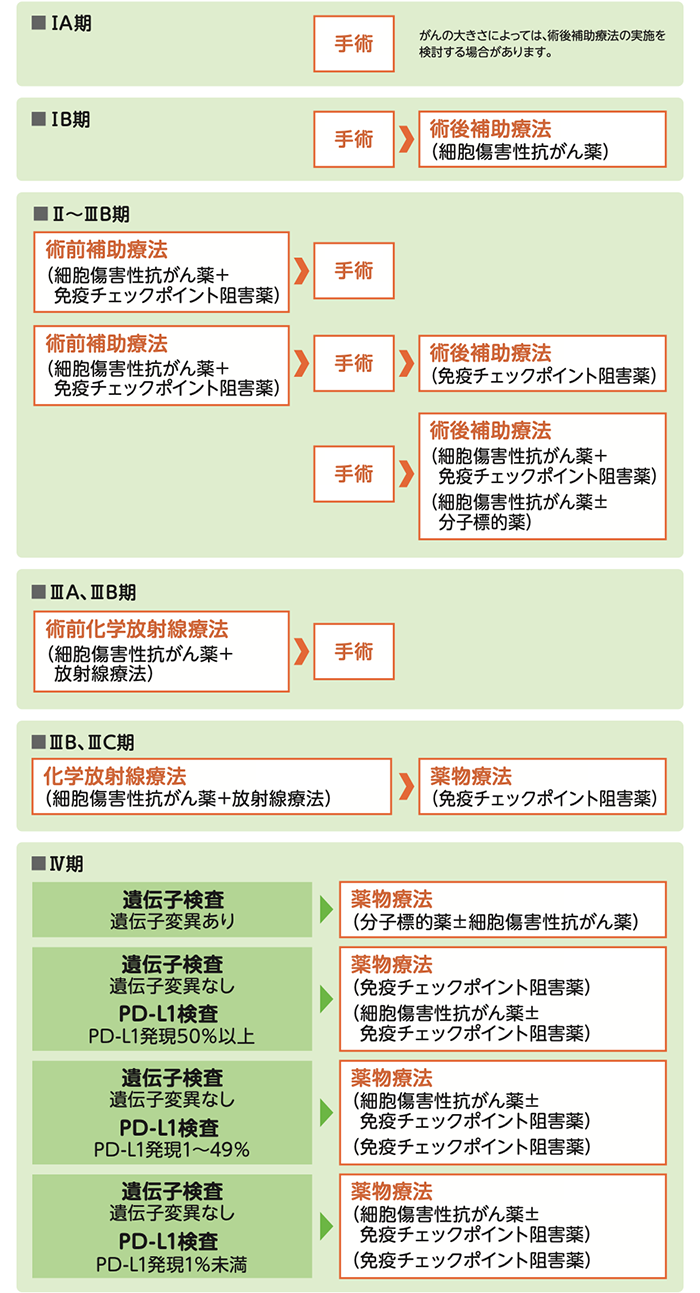

肺がんの種類と進行度によって変わる治療

肺がんの標準治療は

- ・がん細胞の種類(非小細胞肺がん/小細胞肺がん)

- ・がんの大きさと広がり(進行度:「病期」「ステージ」とも呼ばれる)

によって異なります。

非小細胞肺がん

非小細胞肺がんの標準治療

小細胞肺がん

小細胞肺がんでは、TNM分類も使われていますが、化学放射線療法もしくは薬物療法の治療選択の面からは限局型と進展型との分類によって検討されるのが一般的です。

小細胞肺がんの標準治療

- ※実際の治療は、患者さんの状態や病気の進行具合によって異なるため、この通りとは限りません。

いずれの治療法も大まかな目安で、患者さんの病気の状態や、全身の状態などによって選択されます。